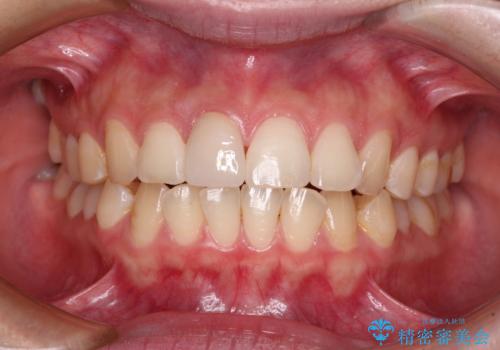

- 転んで前歯が欠けてしまったとのことで来院された患者様です。

転んで前歯の先端1/3ほどが欠けており、近医にて応急処置としてコンポジットレジン修復がされていました。

審美性や舌触り、今後の歯への負担などを考え、オールセラミッククラウンにて補綴治療を行うこととしました。

転倒などの強い力がかかった歯は、歯の内部の歯髄組織が壊死してしまったり、外部吸収と知って、歯根の一部が吸収してしまったりと、思わぬ問題を抱えていることがあります。

治療期間においてはこのようなトラブルは発生していませんでしたが、今後も定期的にレントゲン写真撮影などで経過を見ていく必要があります。